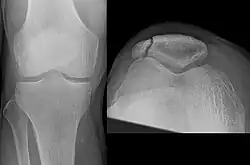

Osteochondral fracture of patella